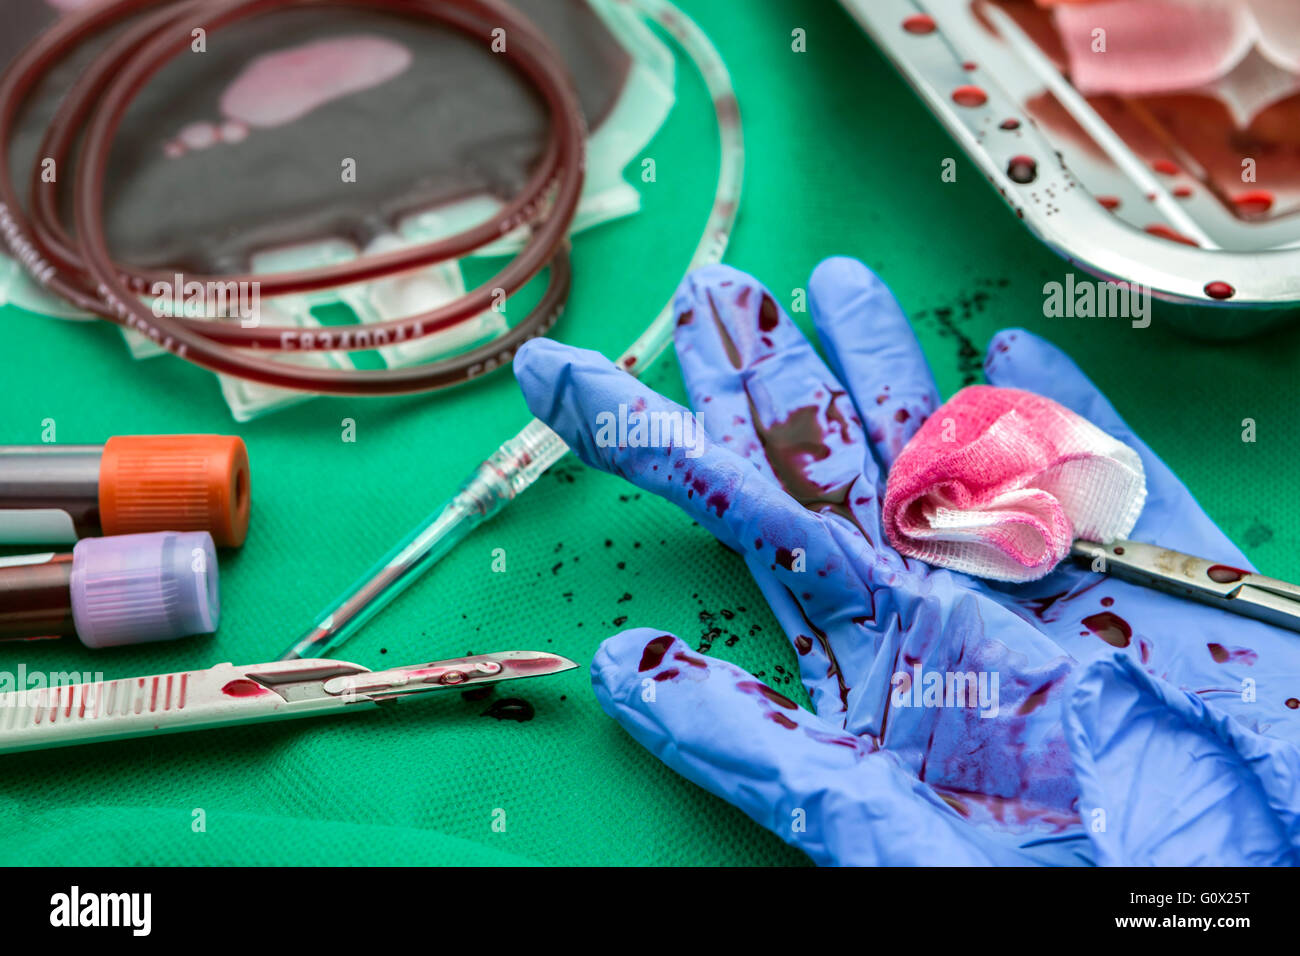

RFG0X245–Einheit der Konzentration der roten Blutkörperchen, blutstillende Kocher Pinzette, Transplantation des oberen Extremität in einem OP-Raum

RFG0X21P–Einheit von Konzentrat roter Blutkörperchen, Transplantation des oberen Extremität in einem OP-Raum

RFG0X25T–Einheit von Konzentrat roter Blutkörperchen, Transplantation des oberen Extremität in einem OP-Raum

RFG0X24W–Einheit der Konzentration der roten Blutkörperchen, blutstillende Kocher Pinzette, Transplantation des oberen Extremität in einem OP-Raum